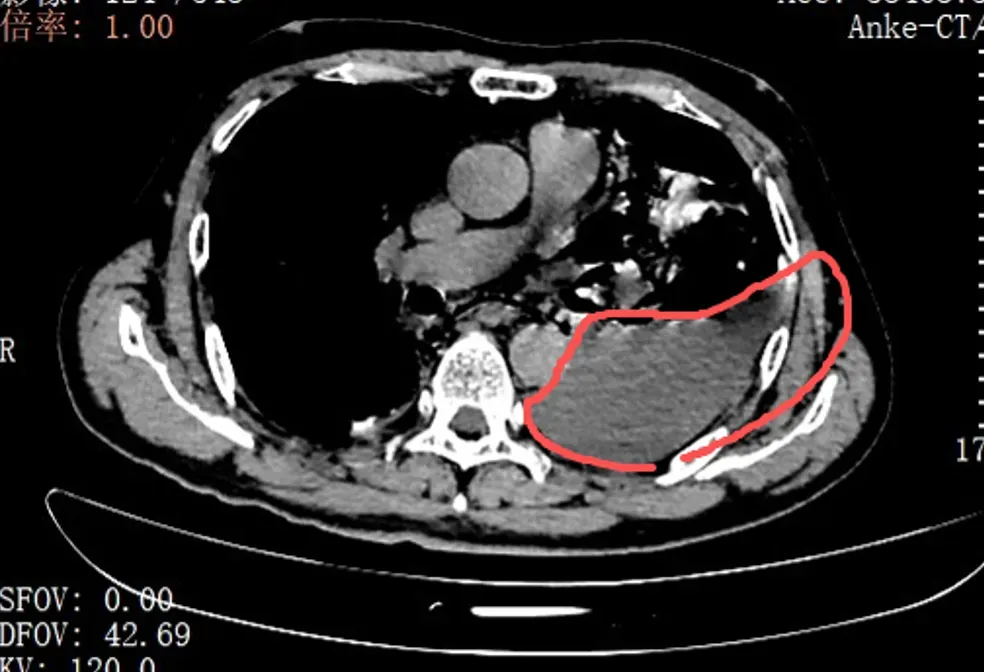

当天,手术团队为张叔实施了胸腔镜下食道修补微创手术。打开胸腔的那一刻,在场的医护人员都愣住了:整个左侧胸腔里,全是叉烧包的菜叶子、食物残渣,混着脓液和消化液,到处都是。

红圈区域是食物残渣、消化液破入食管

手术团队拿着吸引器,一点点清理、冲洗,花了很长时间才将胸腔里的每一点食物残渣都清干净。随后,团队找到了食道下段那道长达10公分的裂口,用可吸收线小心翼翼地完成了分层修补。